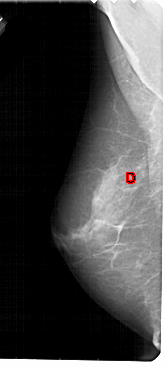

A_1946_1.LEFT_CC

LEFT_CC LINES 4921 PIXELS_PER_LINE 2311 BITS_PER_PIXEL 12 RESOLUTION 43.5 OVERLAY

FILE: A_1946_1.LEFT_CC.OVERLAY

TOTAL_ABNORMALITIES 1

ABNORMALITY 1

LESION_TYPE CALCIFICATION TYPE PLEOMORPHIC DISTRIBUTION CLUSTERED

ASSESSMENT 4

SUBTLETY 3

PATHOLOGY BENIGN

TOTAL_OUTLINES 2

BOUNDARY